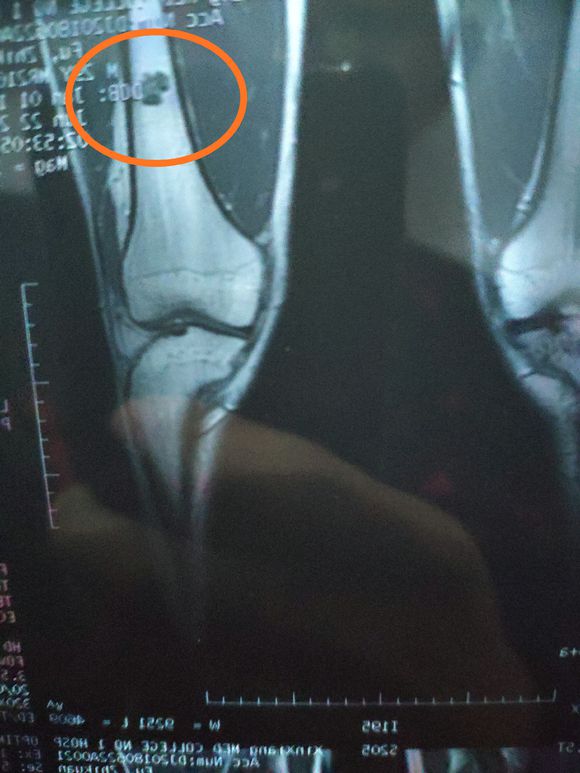

身心俱疲斗争 02019-02-22 患者家属女儿14岁,明天做截肢手术。医生让从髋关节处截,想保留个七八公分。问问大神们髋关节以下留七八公分能用常规的假肢吗? ...

一路向北 02019-01-28 患者家属我孩子今年15岁,年初查出骨肉瘤,左腿关节处,化疗5次做载肢,手术后伤口感染误了化疗,两个多月快三个月发生肺转,如今刚住...

X-man 02019-01-22 患者本人十九岁,九月十号因恶性骨肉瘤在云南省肿瘤医院做了截肢手术,后发现肺上有三个结节,一个大约一厘米,两个不足一厘米,请问...